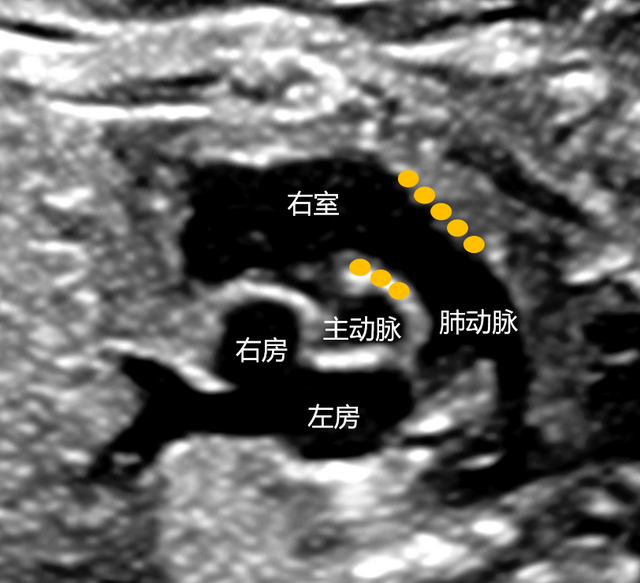

(二)右心室 肺动脉口 动脉圆锥 膜部室间隔 室上嵴 前瓣 三尖瓣 隔瓣

循环系统 脉管系统课件 (四)左心室 右心室左后方,室腔近似圆锥形